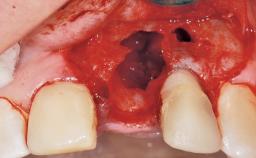

Late Flapless Placement of an Implant in a Maxillary Left Central Incisor Site

A 39-year-old male patient presented with a chief complaint of discomfort and gingival discoloration around his maxillary left central incisor. He was in good general health and was a non-smoker. His past dental history was significant because of the traumatic fracture of tooth 21 in a sporting accident at age 13. Initial dental treatment included endodontic therapy and a full-coverage restoration. The patient became symptomatic 5 years later, when structural failure of the tooth resulted in the dislodgment of the crown. Endodontic retreatment, apical surgery, and post-and-core restoration were performed.

Soft Tissue Anatomy Intact Defective

Bone Volume Horizontally and vertically sufficient Horizontally deficient Deficient vertically or deficient vertically AND horizontally

Bone Volume Deficient horizontally, requiring prior grafting

Soft Tissue Contour and Volume Slightly compromised